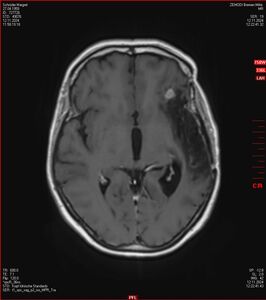

Zum Vergleich nun auch die Bilder vom 1.12.2023:

Ich denke, in den letzen 12 Monaten sind da ein paar Rezidive gewachsen,  vor 12 Monaten waren sie auch schon zu erkennen - vorher noch nicht. Nun hoffe ich auf den Rat des Spezialisten. Hoffendlich kann man etwas machen.